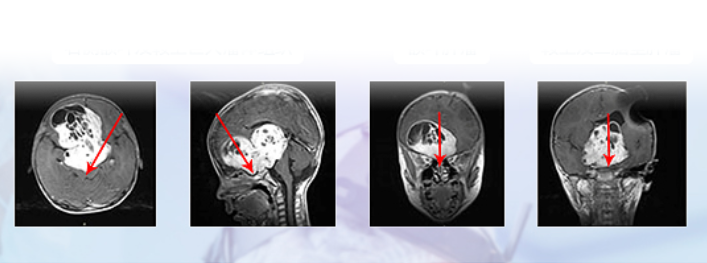

视神经胶质瘤有治愈的案例吗?2018年7月,INC国际神经外科医生集团接到一个咨询电话,年仅5岁的儿童患视神经 胶质瘤 病情严重,访遍国内神经外科医院...

在这条艰难的求医路上,一部分患者在了解到治疗的较大风险后选择了退却,然而另一部分患者认为国际范围内说不定还是有一些较个别的专家教授做起这...

年仅8岁的小伟要面临人生中的二次开颅手术 视路胶质瘤再次复发 原本水汪汪的大眼睛现在也变得混沌 仅能看到一丝光亮 父母一直在感慨走错路了 为何一...